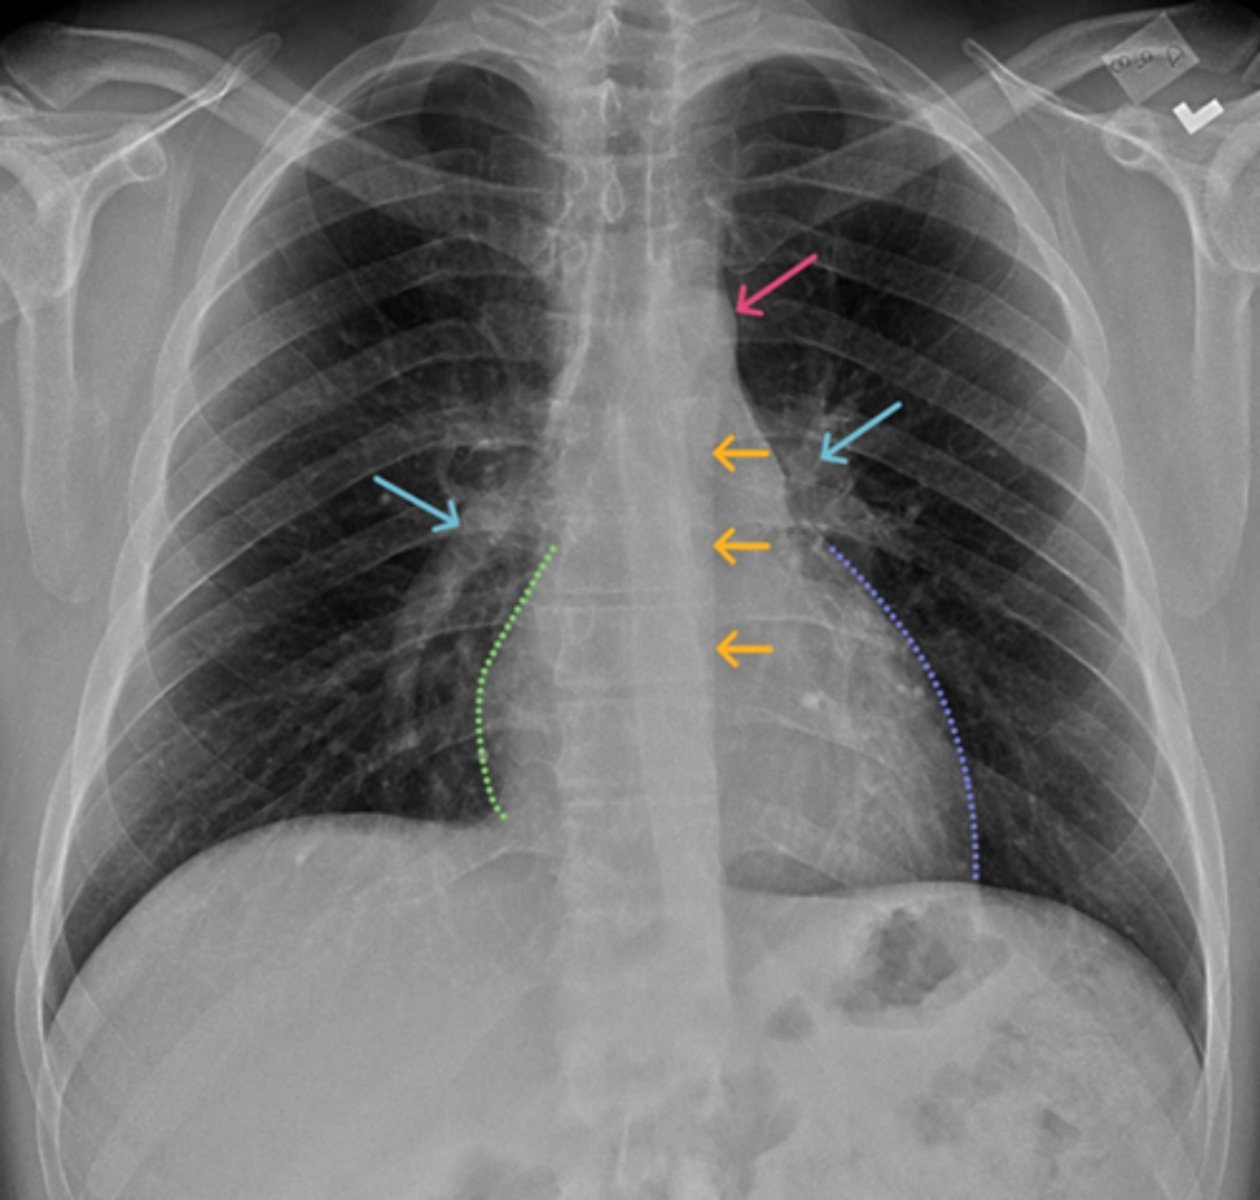

Aortic knob/arch

Pink Arrow

Left ventricle and border of the heart

Purple Line

Pulmonary arteries

Blue Arrows

Normal film

Interpretation